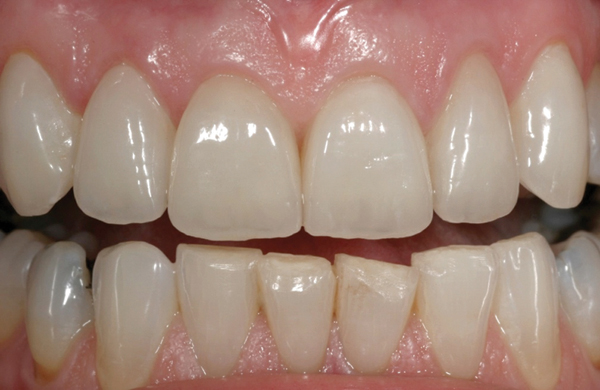

Fig 7. CL-IIa veneers with minimal incisal porcelain layering.

Figure 7

Fig 8. CL-IIa veneers postoperatively (ceramics by Sam Lee, CDT, MDC).

Figure 8

Fig 9. Preoperative view (Fig 9), preparation with composite block-out restoration (Fig 10), and final cementation of CL-IIb material (Fig 11) (final ceramic contour and stain by Steve Lee, CDT, MDC).

Figure 9

Fig 10. Preoperative view (Fig 9), preparation with composite block-out restoration (Fig 10), and final cementation of CL-IIb material (Fig 11) (final ceramic contour and stain by Steve Lee, CDT, MDC).

Figure 10

Fig 11. Preoperative view (Fig 9), preparation with composite block-out restoration (Fig 10), and final cementation of CL-IIb material (Fig 11) (final ceramic contour and stain by Steve Lee, CDT, MDC).

Figure 11

Like all CL-II materials, which have come to be known as glass ceramics, CL-IIa materials can be used for the same indications as CL-I materials—including anterior teeth, bicuspids, and, on rare occasions, molars. Additionally, they have documented long-term clinical success in higher stress situations or when more dentin is exposed. They may be highly translucent, but traditionally they have required slightly thicker dimensions for workability and esthetics/shade matching (ie, minimum working thickness of 0.8 mm if layered with a veneering porcelain) (Figure 7 and Figure 8).20,21

Materials in this subcategory demonstrate increased material strength, primarily due to the processing technique of using a dense, industrial-made block, and possibly due to the leucite and its ability to alter the coefficient of thermal expansion, inhibiting crack propagation. These dense glass- and leucite-containing materials are indicated for thicker veneers, anterior crowns, and posterior inlays and onlays, but only when a long-term bond and seal can be maintained.

An example of this material subcategory is lithium disilicate (eg, IPS e.max®, Ivoclar Vivadent), a glass ceramic material composed of silica, lithium dioxide, alumina, potassium oxide, and phosphorous pentoxide. After the crystalline component has reached optimal growth through the manufacturing process, it is pulverized into powder and processed through a variety of different techniques.23 Lithium disilicate is indicated for the same clinical situations as other glass ceramics; however, when fabricated to a full-contour monolithic restoration and seated with resin cement, it is also appropriate for higher stress situations, such as those requiring full crowns, even on molars (Figure 9 through Figure 11).

Restorations fabricated from this material subcategory demonstrate high strength, fracture resistance, and natural-looking esthetics,24 yielding a versatile and strong alternative for a wider variety of indications. They are indicated when higher risks are involved (eg, less than 50% enamel remains on the tooth, less than 50% of the bonded substrate is enamel, and/or when 30% or more of the margin is in dentin).

Due to the material’s glass properties, adhesive bonding is recommended. However, bonding to dentin results in less predictable restorations due to dentin’s flexibility; restorations bonded to enamel are much more predictable, given enamel’s significant stiffness compared to dentin.19